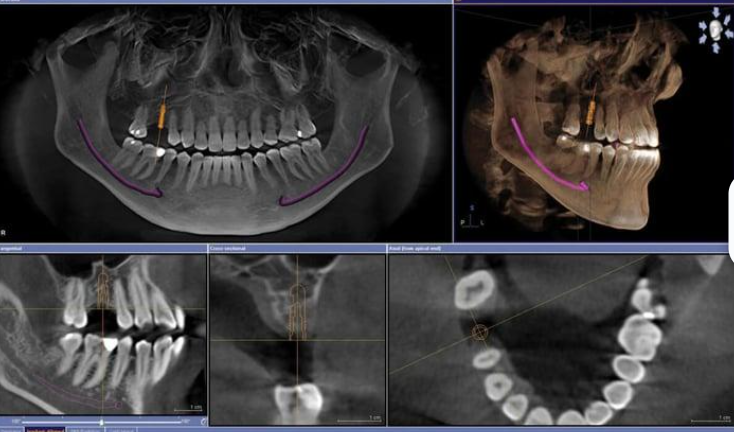

In a dental X-ray or imaging procedure, you'll generally be asked to sit or lie down while the X-ray equipment takes pictures of your mouth and teeth. This process is not painful and is usually completed in just a few minutes.